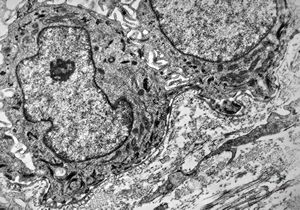

F,23y. | normal oral mucosal epithelium